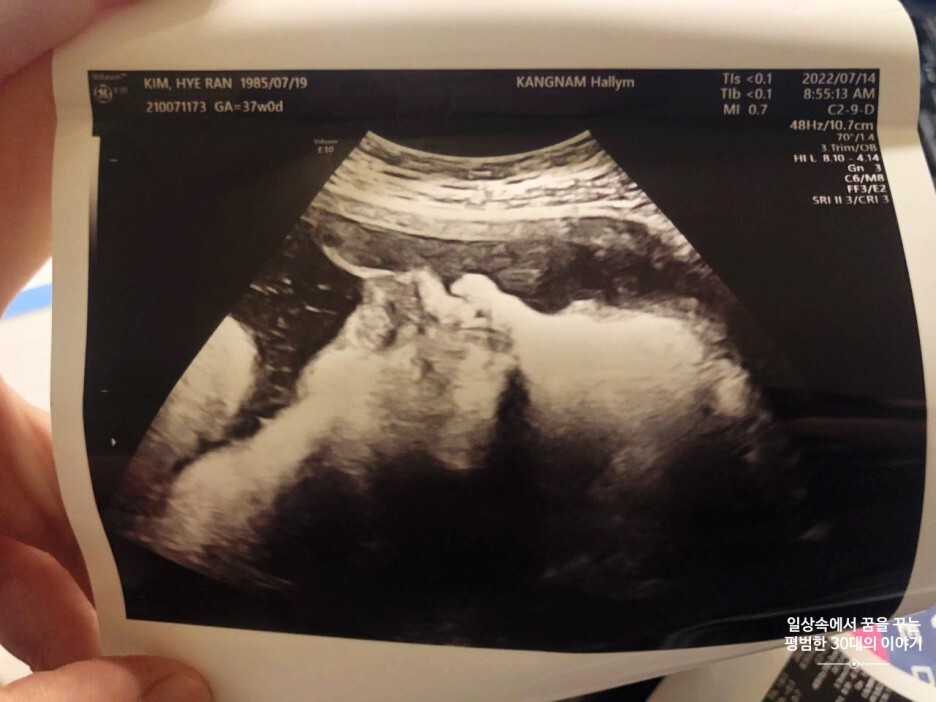

7월 14일 목요일(37주 차 0일)

BPD(Biparietal Diameter, 위에서 볼 때 태아 머리 단면의 가장 긴 길이): 9.05cm

HC(Head Circumference, 태아 머리둘레): 32.92cm

AC(Abdominal Circumference, 배 둘레): 35.18cm

EDD(Expected Date of Delivery, 출산 예정일): 2022년 8월 4일

FL(Femur Length, 허벅지뼈 길이): 6.94cm

GA(Gestational Age, 임신 주차): 37주 차 0일

EFW(Estimated Fatal Weight, 태아 예상 체중)=EBW(Estimated Body Weight): 3326g

FHR(Fetal Heart Rate, 심장박동 수): 140bpm

CL(Cervical Length, 자궁경부 길이): 정상

AF(Amniotic Fluid, 양수): 정상